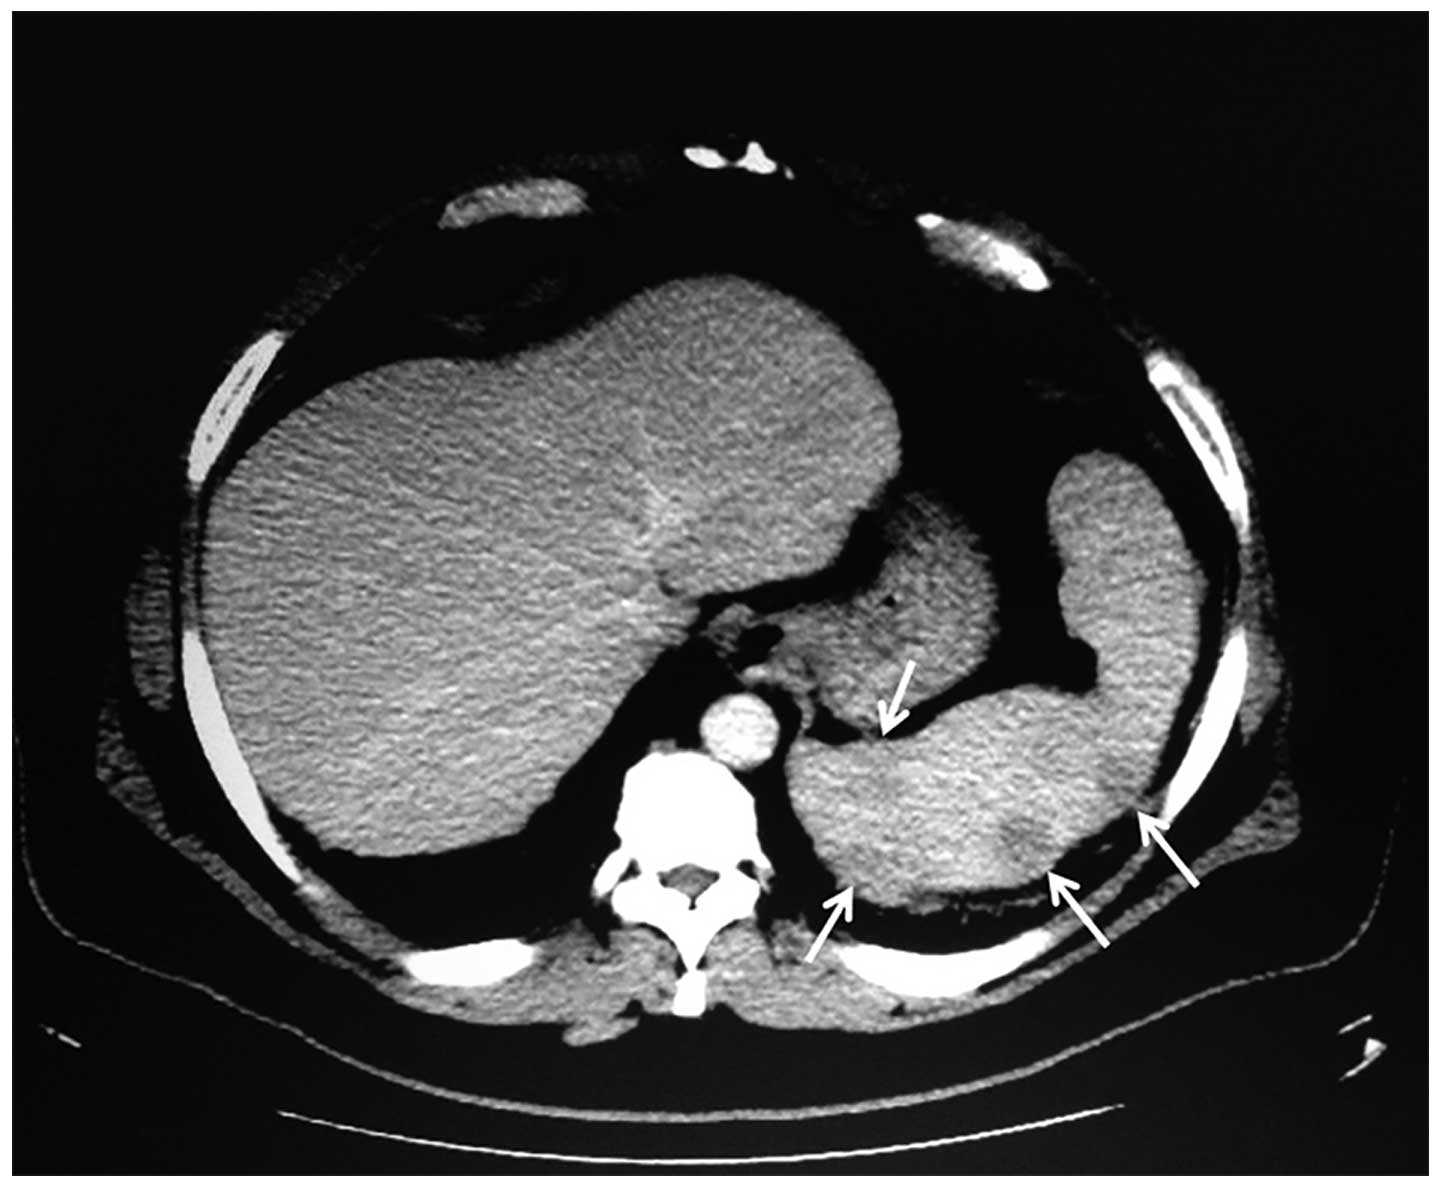

Лимфома яичка диагностика - фото презентация